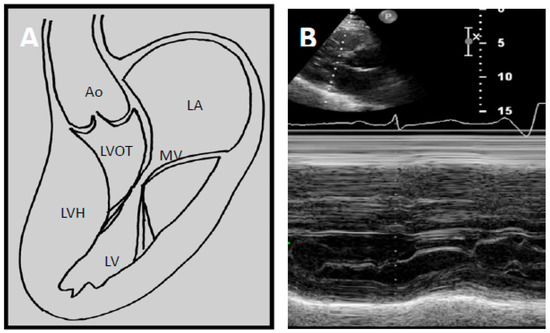

Two factors contribute to LVOTO; hypertrophy of the basal septum and systolic anterior motion (SAM) of the mitral leaflet. In HCM, the mitral valve architecture is abnormal, characterised by leaflet elongation, anterior displacement of the apparatus and papillary muscle abnormalities (Figure 2A). These characteristics make the mitral valve more susceptible to surrounding mechanical forces. As blood flows through the left ventricle in the presence of basal septal hypertrophy, it is directed posteriorly towards the mitral leaflets and then back anteriorly towards the LVOT [34,35]. When blood flows back towards the LVOT, it drags the mitral apparatus, resulting in an anterior motion of the leaflets. This SAM of the mitral leaflets is further reinforced by the Venturi effect produced by the higher velocity of blood flow induced by a narrower LVOT. As the mitral leaflets move anteriorly, they are directed towards the hypertrophied septum, touching the septum in severe instances.

Figure 2.

(A) Schematic demonstrating how left ventricular hypertrophy (LVH) with unfavourable mitral valve anatomy may result in obstruction of the left ventricular outflow tract. Echocardiography allows high quality imaging of the left ventricular outflow tract due to systolic anterior motion of the anterior mitral valve leaflet; (B) Abnormal motion of the mitral valve is well demonstrated on M-mode echocardiography. This may result in high velocities through the LVOT seen on continuous wave Doppler imaging as seen in (C). LA—Left atrium. MV—Mitral valve. LV—Left ventricle. LVOT—Left ventricular outflow tract, LVH—Left ventricular hypertrophy, Ao—Aort.

Echocardiography has transformed diagnostic testing in cardiology. In 1969, Moreyra et al. pioneered the use of echocardiography in diagnosing HCM [21]. The idea of SAM of the mitral leaflet in systole contributing or causing LVOT obstruction was first postulated by Bjork in 1965 at a symposium in London [20]. Due to the lack of supporting evidence at the time, this view was initially unpopular. However, this changed as subsequent angiographic contrast studies demonstrated a characteristic SAM of the mitral leaflet in systole leading to LVOT obstruction [37,38,39]. In 1969, Shah et al. confirmed the finding of SAM of the mitral leaflet using echocardiography and found it to be distinctive of HCM [22] (Figure 2B). The introduction of 2D echocardiography in 1972 allowed direct visualisation of the aortic valve and LVOT, allowing the non-invasive distinction of HCM and aortic stenosis [23].

Two-dimensional (2D) echocardiography has long been the mainstay initial modality of choice in HCM diagnosis. It is used to outline cardiac structures and assess valvular and cardiac function. Doppler echocardiography at rest and during Valsalva manoeuvre is recommended to detect evidence of resting or latent LVOTO (Figure 2C). Left ventricular ejection fracture (LVEF) is usually normal or supra-normal in HCM, while the internal cavity left ventricular (LV) systolic dimensions are often small. As such, myocardial strain may be a better measure of systolic function than LVEF in HCM. Myocardial strain may be measured with Doppler myocardial strain imaging and 2D speckle-tracking technology [40]. Indeed, reduced LV myocardial strain in HCM has been shown to be associated with NSVT, appropriate ICD discharges and cardiac death [41,42,43]. Echocardiography provides detailed assessment of diastolic function, which is often abnormal in HCM.